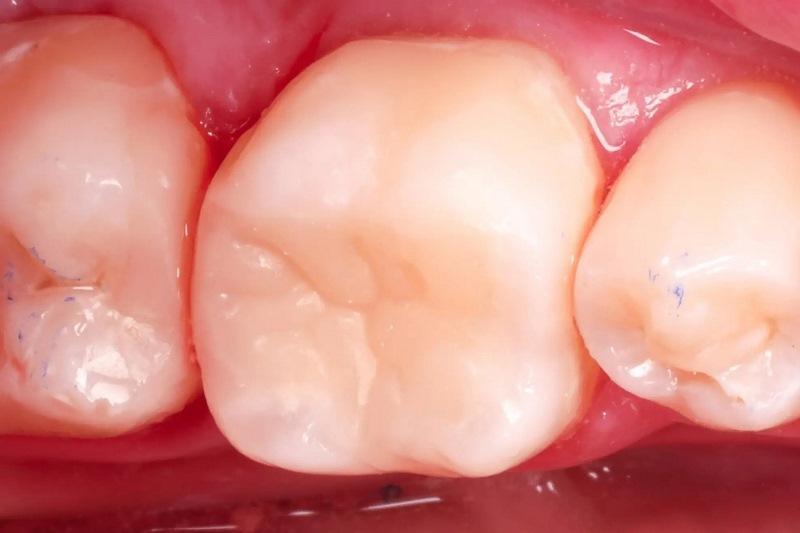

Лечение было сосредоточено на первом моляре нижней челюсти с использованием существующих композитных реставраций I и V классов (фото 1). Состояние зуба протекало бессимптомно, и фриз-тест показал нормальную реакцию. Дистальное кариозное поражение, которое не было клинически заметно, было впервые заподозрено во время планового обследования, и его протяженность была четко определена на панорамной рентгенограмме (фото 2).

Фото 1: Предоперационный снимок первого моляра нижней челюсти с композитными реставрациями.